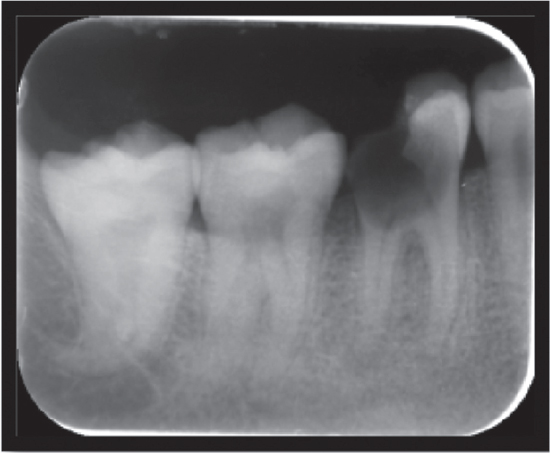

A 26-year-old female patient presented to the Faculty of Dental Sciences at King George’s Medical University, Lucknow, with the primary complaint of pain and sensitivity in the right lower posterior region persisting for the past 3 months. The pain was triggered by mastication and was relieved thereafter. A radiograph (IOPA) revealed periodontal bone loss affecting the coronal third of the distal root compared to the mesial root, and it showed periapical radiolucency at the distal root [Figure 7]. The periodontal support of the mesial root of tooth 46 was deemed adequate. Based on these findings, the diagnosis of chronic irreversible pulpitis associated with the lower right mandibular molar, along with furcation involvement, was established [Figure 8]. It was determined that the distal root should undergo hemisection subsequent to the completion of endodontic therapy for the tooth, in accordance with the methodology employed in Case 1 [Figures 9]. The hemisection of the distal root was executed using a vertical cut technique to effectuate separation. The crown was sectioned using a tapered fissure carbide bur until it reached the furcation. The procedure was thoroughly elucidated to the patient, and informed consent was duly obtained. Following the administration of local anesthesia, a mucoperiosteal flap was reflected to expose the area designated for hemisection. The hemisection procedure was performed on tooth 46 [Figure 10], after which the flapwas repositioned and sutured using 3-0 silk nonresorbable interrupted sutures. Definitive restorative therapy was conducted 6 weeks after the hemisection, which involved the placement of a three-unit porcelain fused-to-metal fixed partial denture to replace the distal root of the mandibular first molar, second premolar, and second molar [Figure 11]. At the 1-year follow-up appointment, the patient reported being asymptomatic.

Figure 10. Hemisection of distal root

thumb

This case report presents a detailed examination and treatment of a severely damaged tooth exhibiting furcation involvement. In our case, tooth was effectively treated through hemisection, a powerful alternative to extraction that preserves natural tooth structure and promotes better long-term outcomes. The remaining roots underwent root canal therapy and were restored with suitable materials and then splinted to an adjacent tooth to prevent displacement. A fixed prosthodontic prosthesis was subsequently placed to maintain occlusal balance. The hemisection procedure allows physiologic tooth mobility of the remaining root, which is more suitable abutment for fixed partial dentures.[5] Root amputation is a useful alternative treatment to save those decayed multi-rooted teeth which have been indicated for extraction.[6] Before selecting a tooth for hemisection, the patient’s oral hygiene status and medical status should be considered, and the accessibility of root furcation for ease of operation as well as good bone support for the remaining roots should be assessed.[7] The furcation region is carefully smoothed to allow proper cleaning to prevent accumulation of food lodging.[8] Root fracture is the main cause of failure after hemisection, so occlusal modification is required to balance the occlusal forces on the remaining root.[9] Contraindications include the presence of a strong abutment tooth adjacent to the proposed hemisection, which could act as an abutment to the prosthesis.[10] Hemisection has been used successfully to retain teeth with furcation involvement. However, there are few disadvantages associated with it. As with any surgical procedure, it can cause pain and anxiety. Root surfaces that are reshaped by grinding in the furcation or at the site of hemisection are more susceptible to caries. Often, a favorable result may be negated by decay after treatment. Failure of endodontic therapy due to any reason will cause failure of the procedure[11] Furthermore, there are conflicting data about the survival of the remaining fragment (3%-38% for 10 years) and a wide range of reasons for the failure of hemisection[12] According to Buhler et al. hemisection should be considered before every molar extraction because this procedure can provide good absolute biological cost savings with good long-term success.[13] In the present case, good prognosis was observed with proper occlusion, the absence of mobility, and healthy periodontal tissues. Concurring with previous reports, hemisection is a valid treatment option for the molar teeth in a young patient, which otherwise have to be extracted due to extensive caries [Figures 9-11].